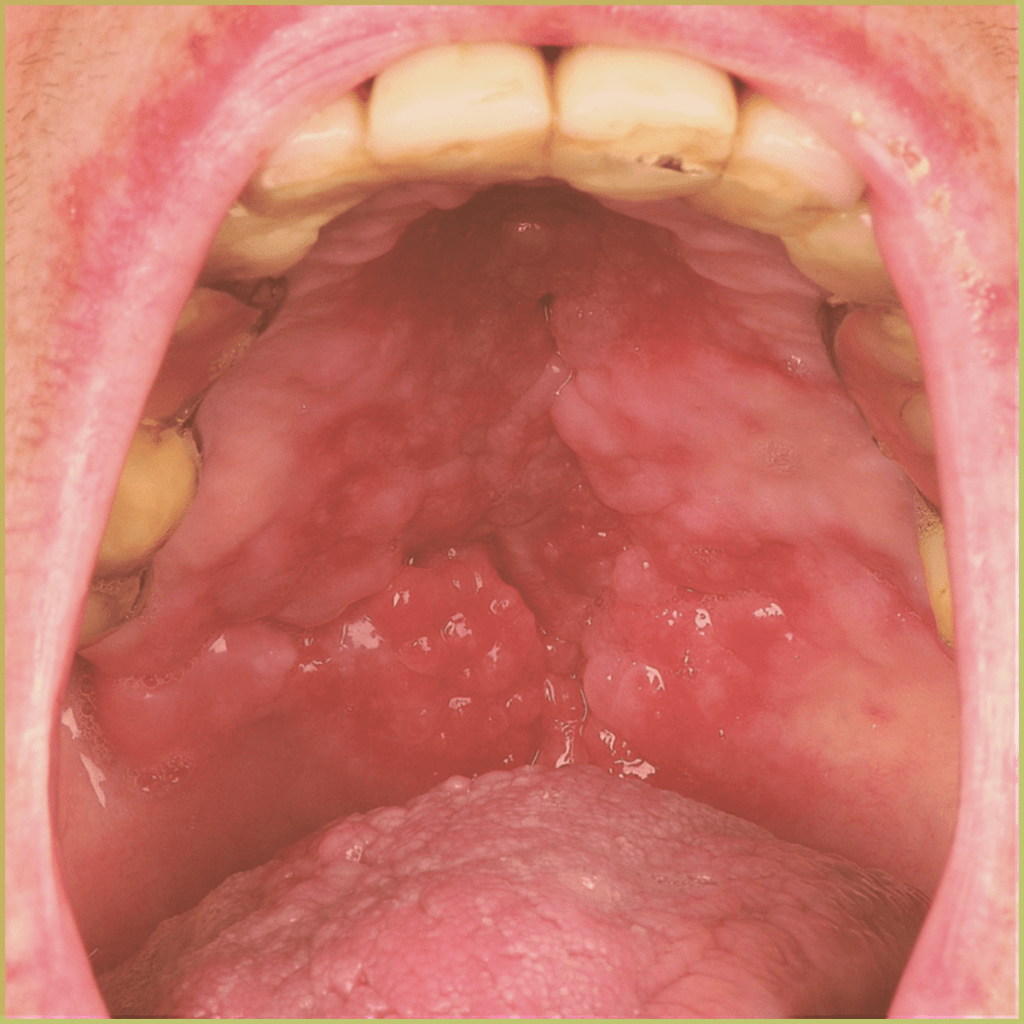

CROHN'S DISEASE

Crohn’s Disease is a subtype of inflammatory bowel disease (IBD) that causes chronic relapsing transmural inflammation of any section of the gastrointestinal tract, leading to abdominal pain, diarrhea, obstruction, weight loss and/or perianal lesions. The cause of Crohn’s disease is unknown and the condition is progressive and destructive. The common clinical presentation includes:

- Oral granulomas (submucosal nodules).

- Polypoid masses with fissures and ulceration along the buccal/labial sulcus.

- Aphthous-like oral ulcers.

Diagnosis is based on the lesion history, clinical presentation and microscopic findings, which may include non-caseating epithelioid granulomas within submucosa. Your differential diagnosis should include

- Fungal or mycobacterial infections.

- Tertiary syphilis and other treponemal infections.

- Major aphthous ulcers

Treatment options include:

- Palliative management of intestinal symptoms.

- Non-steroidal anti-inflammatory drugs and/or systemic corticosteroids.

- Intralesional corticosteroid injections.